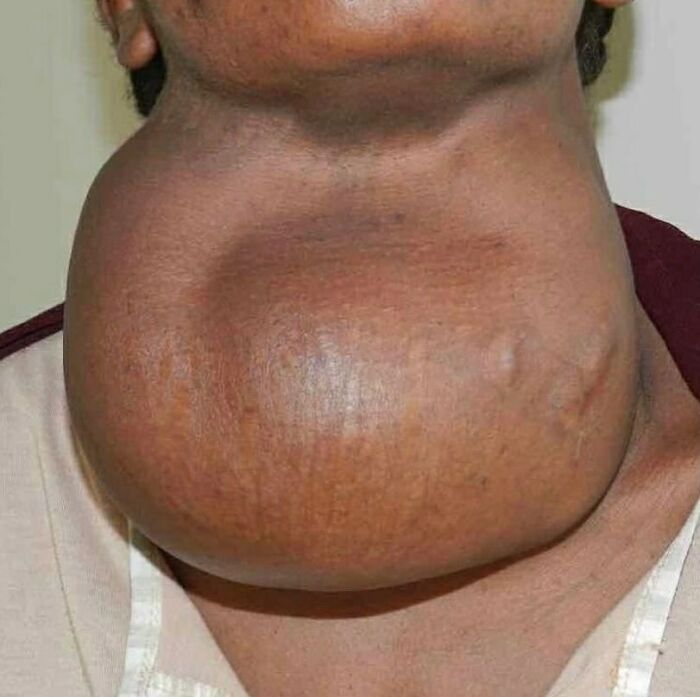

A patient with severe goiter. A goiter, is a swelling in the neck resulting from an enlarged thyroid gland.